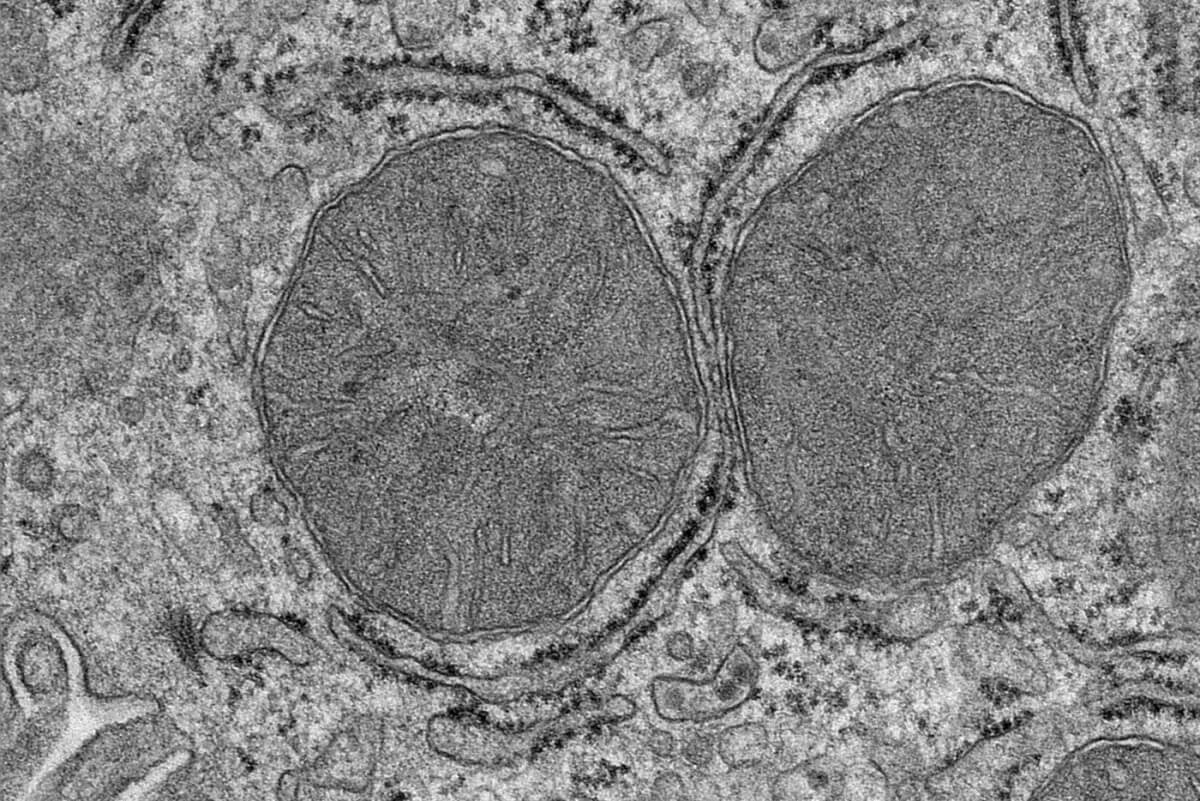

“When our senses detect food, our body prepares for food intake by producing saliva and digestive acid. We knew from previous studies that the liver also prepares for food intake. Now we have taken a closer look at the mitochondria in liver cells, because they are essential cell organelles for metabolism and energy production, and realized how surprisingly fast this adaptation takes place,” explains Sinika Henschke, the first author of the study, in a media release.

Using mice, the researchers showed that just seeing and smelling food was enough to stimulate a response in the liver. More specifically, sensing food impacted the mitochondria in the liver cells, which is mediated by a previously uncharacterized phosphorylation in a mitochondrial protein.

The impact on the liver is mediated by a group of nerve cells called POMC neurons, which are activated within mere seconds by just the sight and smell of food. The liver is then signaled to prepare for nutrients to come its way. The team’s research also shows that the activation of POMC neurons alone is enough to adapt the mitochondria, even without food around.